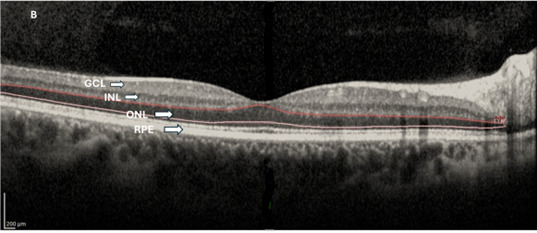

Background/Objectives: To evaluate the associations between corneal topographic irregularity, higher-order aberrations (HOAs), and posterior segment structural and microvascular parameters in keratoconus using optical coherence tomography (OCT) and OCT angiography (OCTA). Methods: In this cross-sectional study, 81 eyes with keratoconus and 60 healthy [...] Read more.

Background/Objectives: To evaluate the associations between corneal topographic irregularity, higher-order aberrations (HOAs), and posterior segment structural and microvascular parameters in keratoconus using optical coherence tomography (OCT) and OCT angiography (OCTA). Methods: In this cross-sectional study, 81 eyes with keratoconus and 60 healthy control eyes underwent corneal topography and wavefront analysis, spectral-domain OCT with enhanced depth imaging, and OCTA. Retinal layer thicknesses, choroidal thickness and area metrics, choroidal vascularity index (CVI), and OCTA-derived vascular parameters were analyzed. Associations were assessed using Spearman correlation analysis with false discovery rate (FDR) correction. Results: Compared with controls, keratoconus eyes showed significantly increased corneal curvature, corneal irregularity indices, and HOAs (all p < 0.001). Structural OCT analysis demonstrated preserved inner retinal layers, whereas outer nuclear layer thickness was reduced (p < 0.001) and overall outer retinal layer thickness was increased (p = 0.005). Choroidal thickness and both total and luminal choroidal areas were significantly greater in keratoconus eyes (all p ≤ 0.011), while CVI did not differ between groups (p > 0.05). OCTA revealed reduced superficial capillary plexus vessel density at the whole image and perifoveal regions (all p < 0.001), whereas deep capillary plexus and foveal avascular zone metrics were largely preserved. Correlation analyses identified only weak and inconsistent associations between corneal parameters, HOAs, and posterior segment measurements, none of which remained statistically significant after FDR correction. Conclusions: Despite pronounced anterior segment deformation and optical degradation, posterior segment structural and microvascular alterations in keratoconus are limited and weakly related to corneal disease severity. These findings support a predominantly anterior segment centered pathophysiology of keratoconus and highlight the importance of stringent multiple-comparison control in multimodal imaging studies. Full article

Figure 1